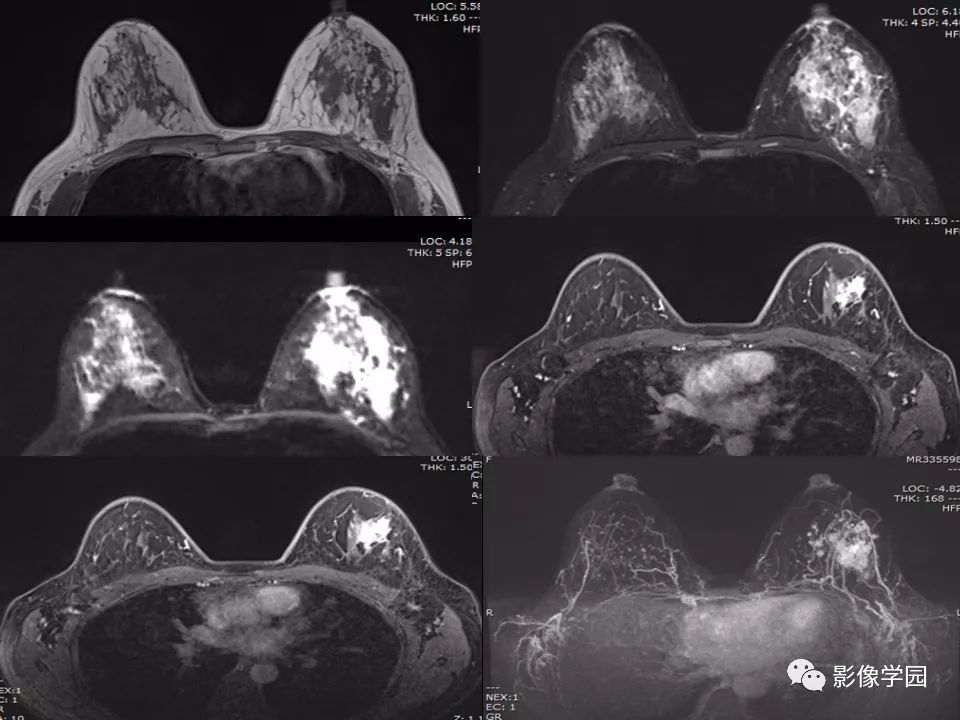

非哺乳期乳腺炎性病变与炎性乳癌影像诊断

图片尺寸960x720